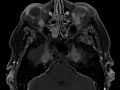

Rosai-Dorfman

There is thick pachymeningeal enhancement along the falx and tentorial leaflets as well as along the medial aspects of the middle cranial fossae extending into Meckel’s caves and foramina ovale along the course of the branches of the V2 and V3 segments of the trigeminal nerves. Enhancement extends into the masticator spaces and pterygopalatine fossae.  Findings can be seen in granulomatous diseases, lyme disease, neurofibromatosis, lymphoma, or histiocytosis.  This case turned out to be CNS Rosai-Dorfman, a benign disease characterized by massive lymphadenopathy and variable extranodal involvement of the dura, sinuses, skin, orbits, bone, and salivary glands. CNS manifestations are usually that of enhancing dural based masses as seen here. The diagnosis is made by biopsy and patients are usually monitored and treated symptomatically with tumor debulking as needed.